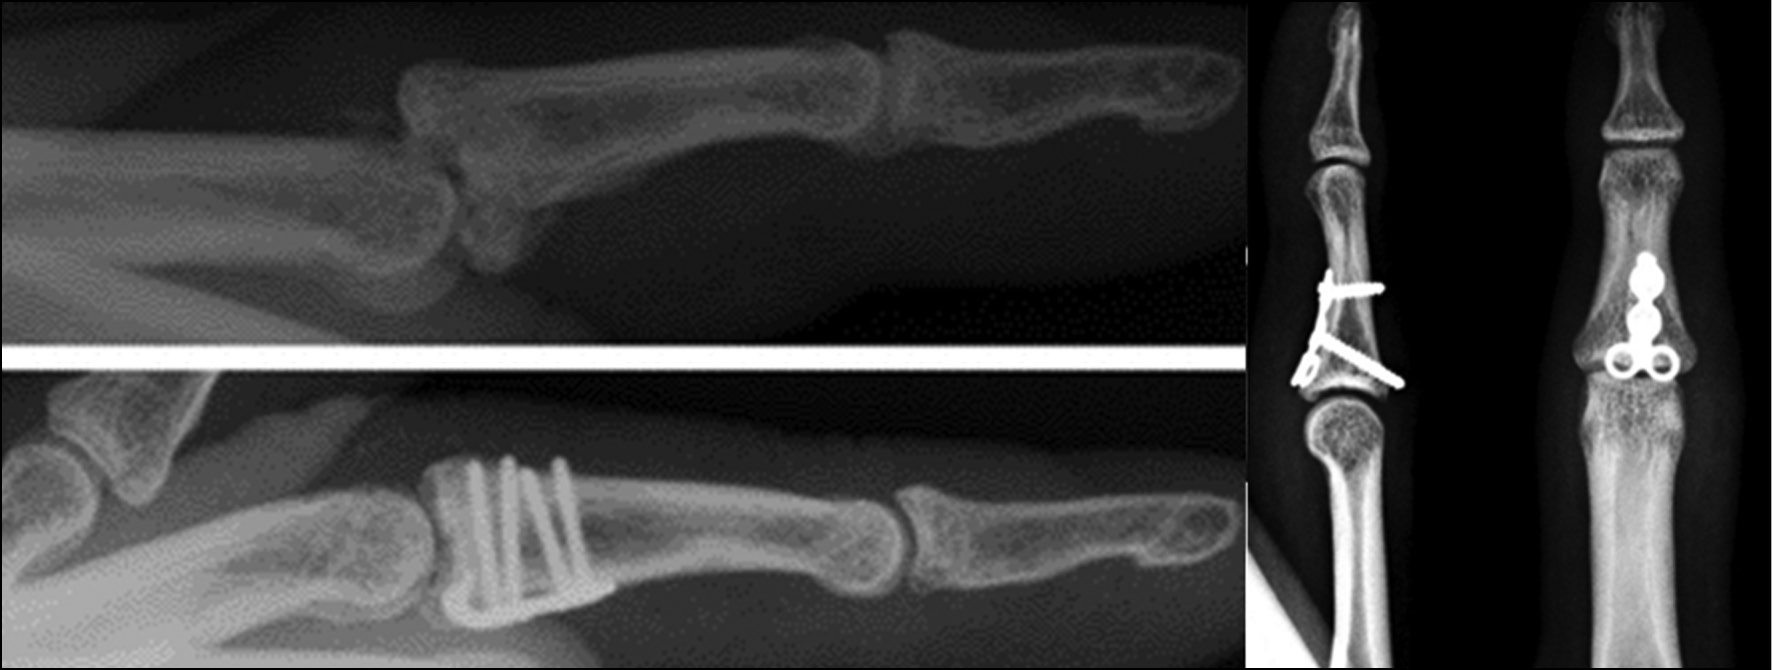

Чрескостный остеосинтез

Описано множество различных видов внешних фиксаторов, статических и динамических (рис. 15) [24].

Рис. 15. Вариативность аппаратов внешней фиксации [3].

Fig. 15. Variation of external fixation devices [3].

Динамические виды, используя механизм лигаментотаксиса от дистракции, позволяют добиться репозиции фрагментов и удерживать её. Благодаря преимуществам динамических фиксаторов были изжиты статические модели, поскольку первые позволяли получить ранние движения, что приводило к лучшим клиническим результатам. Идеальный внешний фиксатор поддерживает репозицию, благодаря дистракции осуществляется лигаментотаксис, он достаточно компактен и обеспечивает раннее восстановление движений. Дистракция достигается благодаря поперечно проведённой спице через центр ротации в головке проксимальной фаланги [5]. Описаны аппараты внешней фиксации, состоящие из спиц Киршнера, которые моделировались определёнными способами для достижения идей каждой отдельной методики. Конгруэнтность суставной поверхности достигалась за счёт дистракции и нужного репозиционного момента, создаваемых в условиях внешних фиксаторов [7]. В 1994 году Suzuki с соавт. опубликовали работу, в которой представили аппарат наружной фиксации, состоящий из 3 спиц и резиновых колец (рис. 16) [25].

Гемиартропластика

Пластика основания средней фаланги костным аутотрансплантатом крючковидной кости (рис. 17) обеспечивает стабилизацию ладонной пластинки, раннюю мобилизацию за счёт жесткой фиксации и пластику повреждённой хрящевой поверхности [5]. Данная методика является технически сложной процедурой. Частота осложнений остаётся высокой, а признаки остеоартроза рентгенологически регистрируются в 50% случаев [26]. В 10% наблюдений отмечаются контрактура и резорбция трансплантата [5].

Рис. 17. Этапы гемиартропластики.

Fig. 17. Stages of hemiarthroplasty.